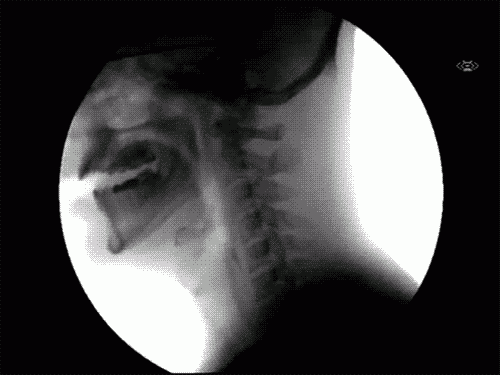

6 Երբ դուք կուլ եք տալիս